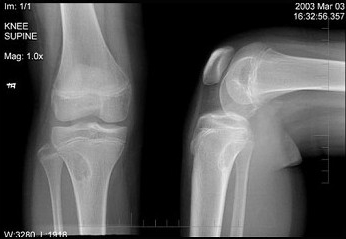

左膝关节酸胀不适,摄片发现左胫骨上段局限性骨质改变如图示,最可能的诊断是()

A:非骨化性纤维瘤

B:骨化性纤维瘤

C:内生软骨瘤

D:骨软骨瘤

E:骨肉瘤